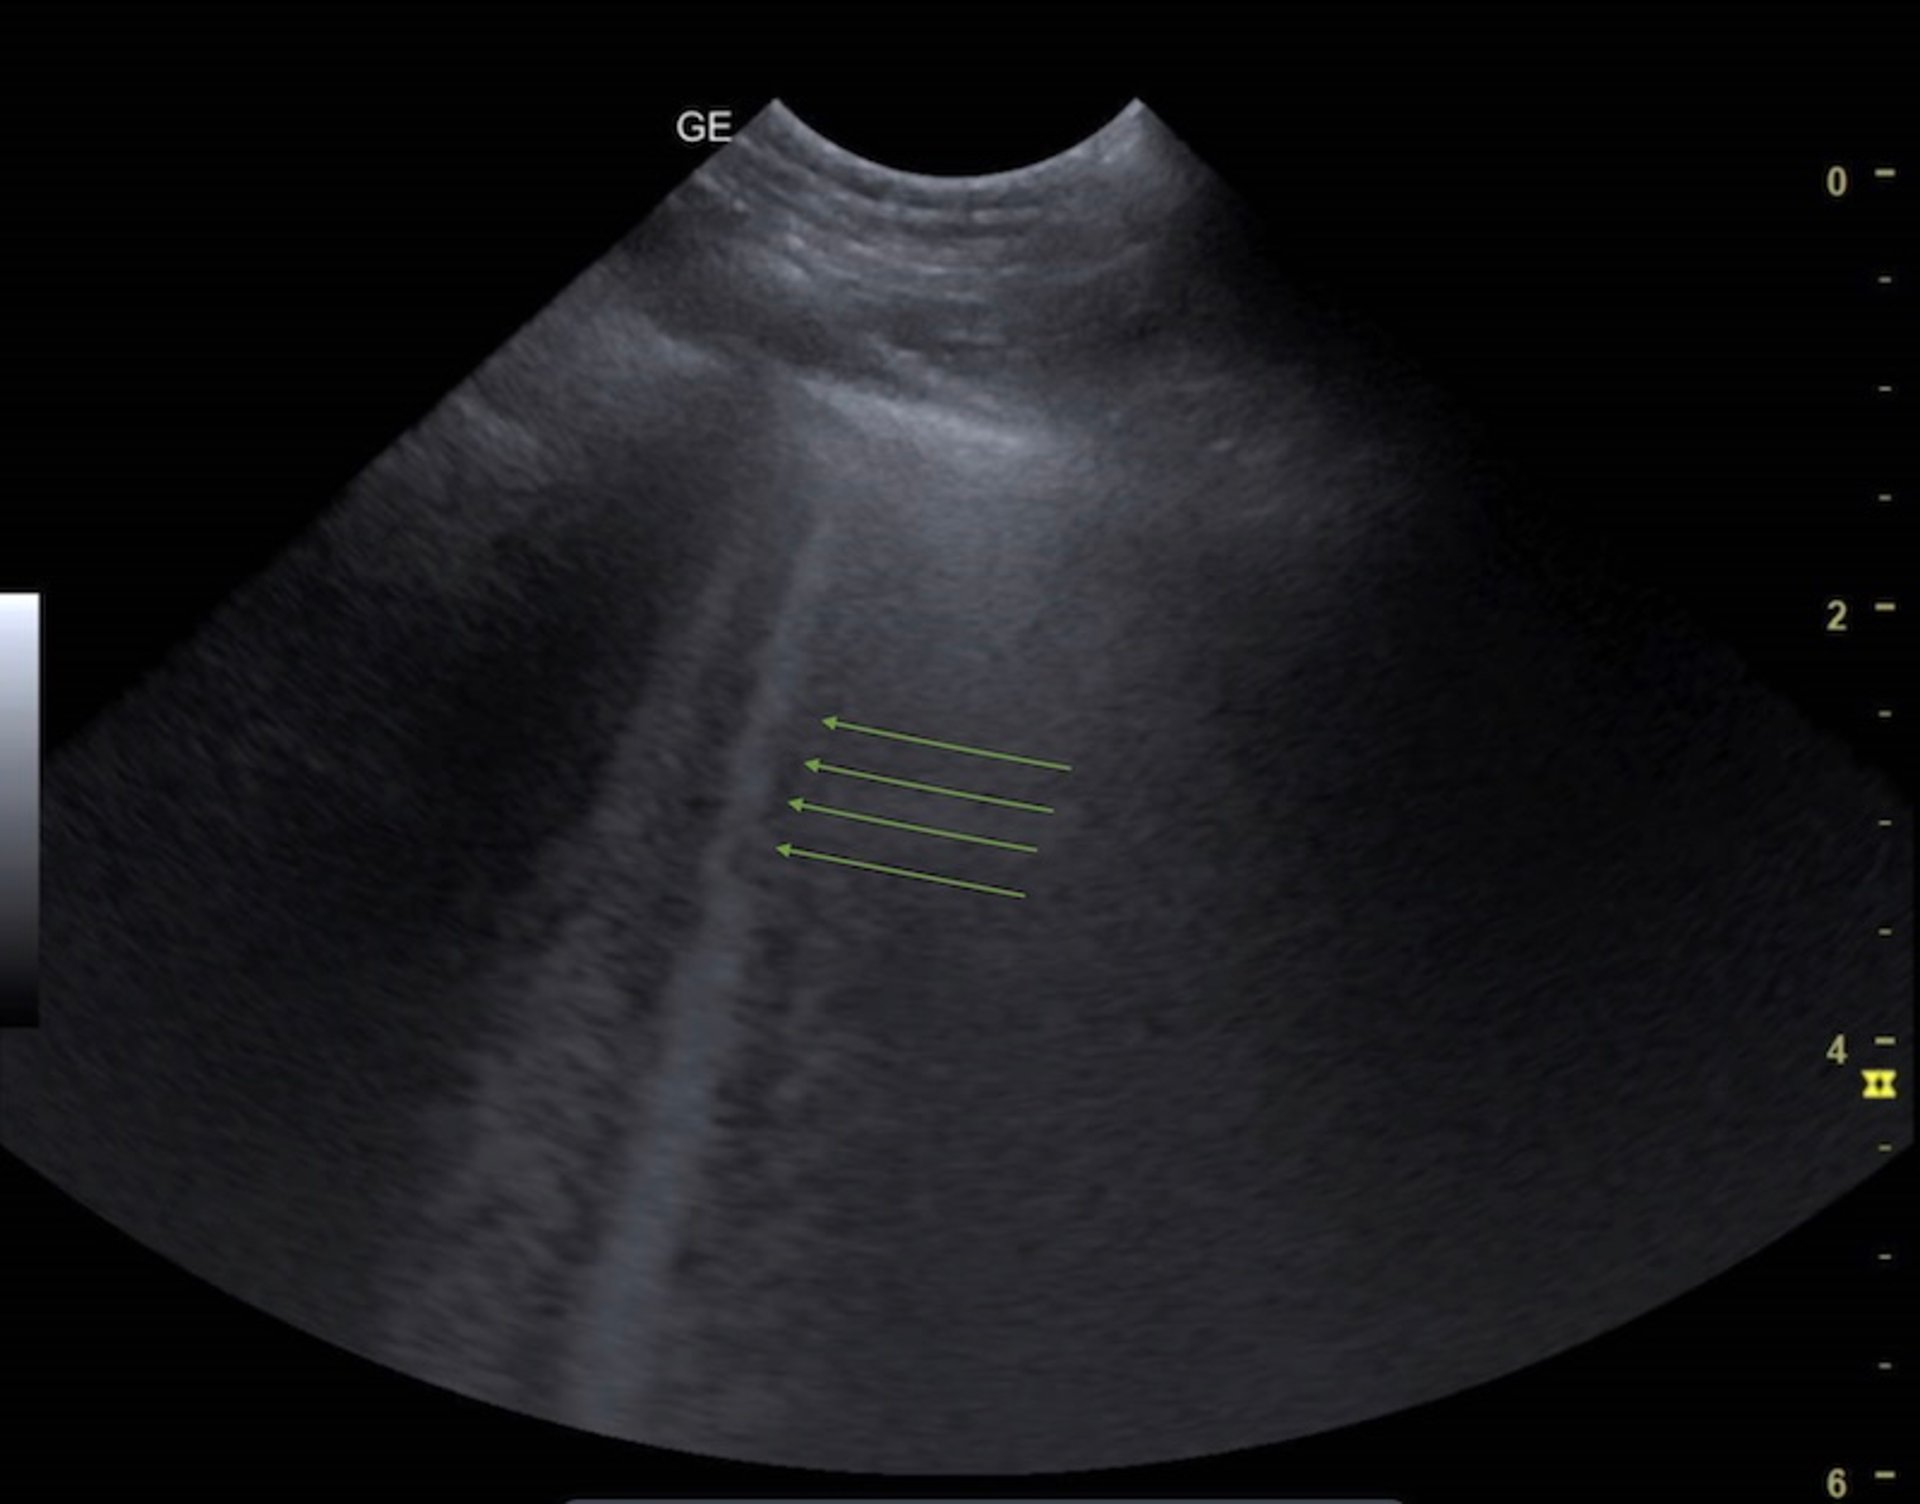

B-lines on a lung ultrasonogram

B-lines are bright (hyperechogenic) vertical artifacts that extend from the pleural interface through the screen. They indicate fluid accumulation within the interstitial space.

Courtesy of Dr. Andrew Linklater.